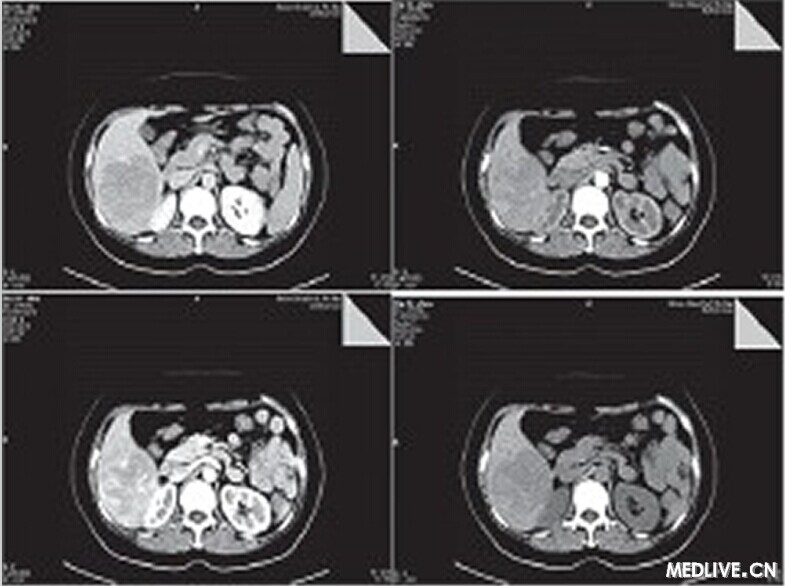

CT檢查平掃示肝右葉見6.6 cm×7.7 cm×8.8 cm塊影,CT值約為49 HU,病變內(nèi)下緣與右腎上極分界欠清。動(dòng)態(tài)增強(qiáng)掃描動(dòng)脈期病變內(nèi)見腫瘤血管影,延遲期呈相對(duì)低密度影,三期CT值分別為55.3 HU、85.8 HU、67.5 HU,腹膜后未見腫大淋巴結(jié)(如圖1所示)。結(jié)論:肝右后葉占位,肝癌可能性大,腹腔積液。

圖1 CT平掃

肝AML的CT影像學(xué)差異較大,主要取決于腫瘤內(nèi)脂肪的含量及異常血管所占的比例,典型病例腫瘤內(nèi)存在脂肪影時(shí),CT值往往為負(fù)值。診斷肝AML不難,但部分肝AML在影像學(xué)上因缺乏脂肪而無特征性表現(xiàn),容易誤診。本病例起初診斷為肝癌,因其較符合肝癌的CT影像學(xué)特點(diǎn):在增強(qiáng)掃描時(shí),表現(xiàn)為“快進(jìn)快出”,動(dòng)脈期明顯強(qiáng)化,可以看到多數(shù)細(xì)條彎曲強(qiáng)化的供血?jiǎng)用}及腫瘤實(shí)質(zhì)區(qū)強(qiáng)化影,于門脈期雖然病灶實(shí)質(zhì)部分仍有強(qiáng)化但病灶內(nèi)動(dòng)脈供血血管消失,于延時(shí)期病灶強(qiáng)化程度降低呈低密度影。

肝AML的CT影像學(xué)差異較大,主要取決于腫瘤內(nèi)脂肪的含量及異常血管所占的比例,典型病例腫瘤內(nèi)存在脂肪影時(shí),CT值往往為負(fù)值,診斷肝AML不難。但部分肝AML在影像學(xué)上因缺乏脂肪而無特征性表現(xiàn),容易誤診。如本病例腫瘤內(nèi)缺少典型脂肪及平滑肌成分,形態(tài)上較為單一,影像學(xué)缺乏典型的血管平滑肌脂肪瘤特征,從而誤診為肝癌,值得引起臨床、影像科以及病理科醫(yī)生的注意。